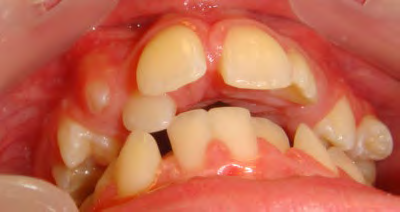

The patient below had severe crowding of both upper canines and the lower right 5. The upper 4’s and 2’s were actually in contact.

Below are cases treated at Vakresmil without extractions within the last three years. The families had been told, “It is simply not possible for your child to be treated without extractions” by orthodontists. Judge for yourself if that was right or wrong.